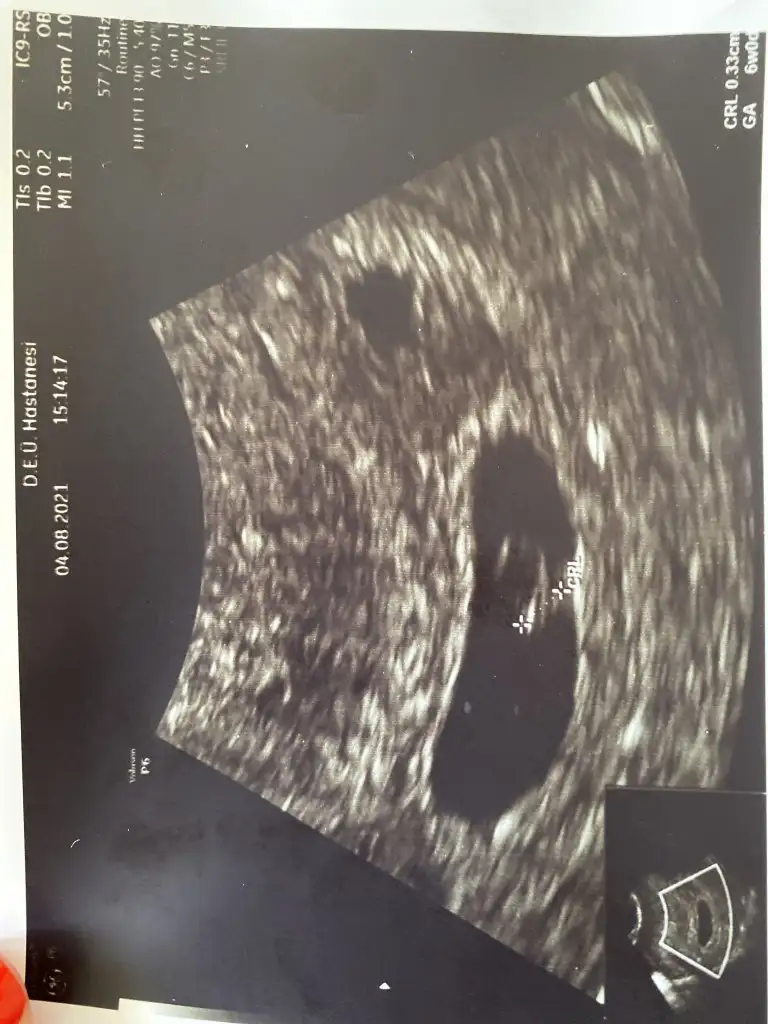

Oyyy kuzum maşallahOhhh çok şükür duyduk sesini devlette vajinal baktılar özelde karından direkt net bir şekilde görüp duydukDarısı başınıza hayırlısıyla.. 6+2 mişiz

Burda yazıyodur ölçülerio da kalp atışı çok şükür herşey yolunda ❤